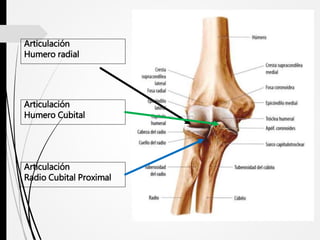

Articulación

Humero radial

Humero Cubital

Radio Cubital Proximal

ARTICULACIÓN DEL CODO (HUMERO RADIAL Y HUMERO CUBITAL).

• Superficies Articulares.

• Capsula Articular.

• Ligamentos.

• Movimientos: Flexión y Extensión

• Irrigación: Anastomosis de arterias que rodean la articulación.

• Inervación: N. Musculo-cutáneo, Radial y Ulnar.

ARTICULACIÓN DEL CODO (RADIOCUBITAL PROXIMAL).

• Movimientos: Supinación y Pronación

• Irrigación: Arterias Periarticulares de la región del codo

• Inervación: N. Musculocutaneo, Mediano y Radial.